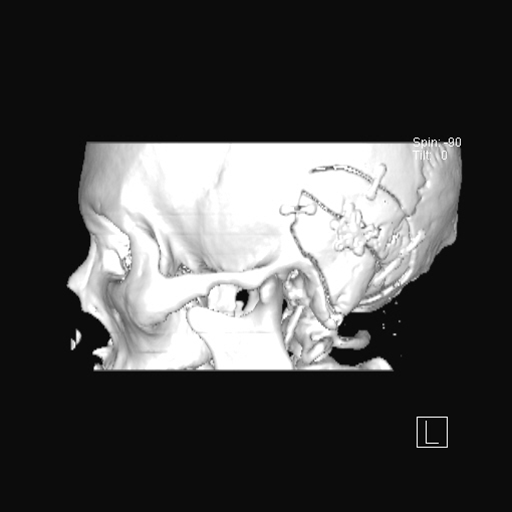

术后CT磨除范围

术后颅骨表面重建